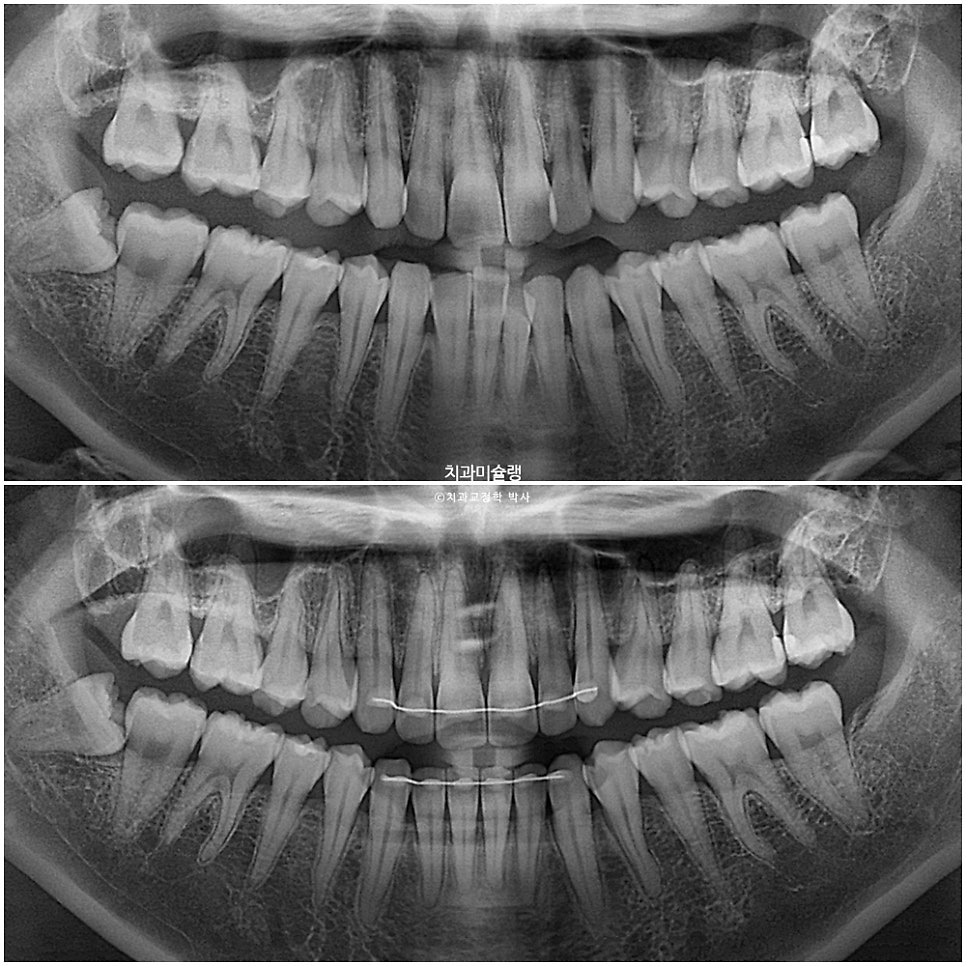

방사선 검사 결과

치료 전후 엑스레이를 볼게요.

치근흡수는 없으며 치아 뿌리 평행도는 개선되었습니다.